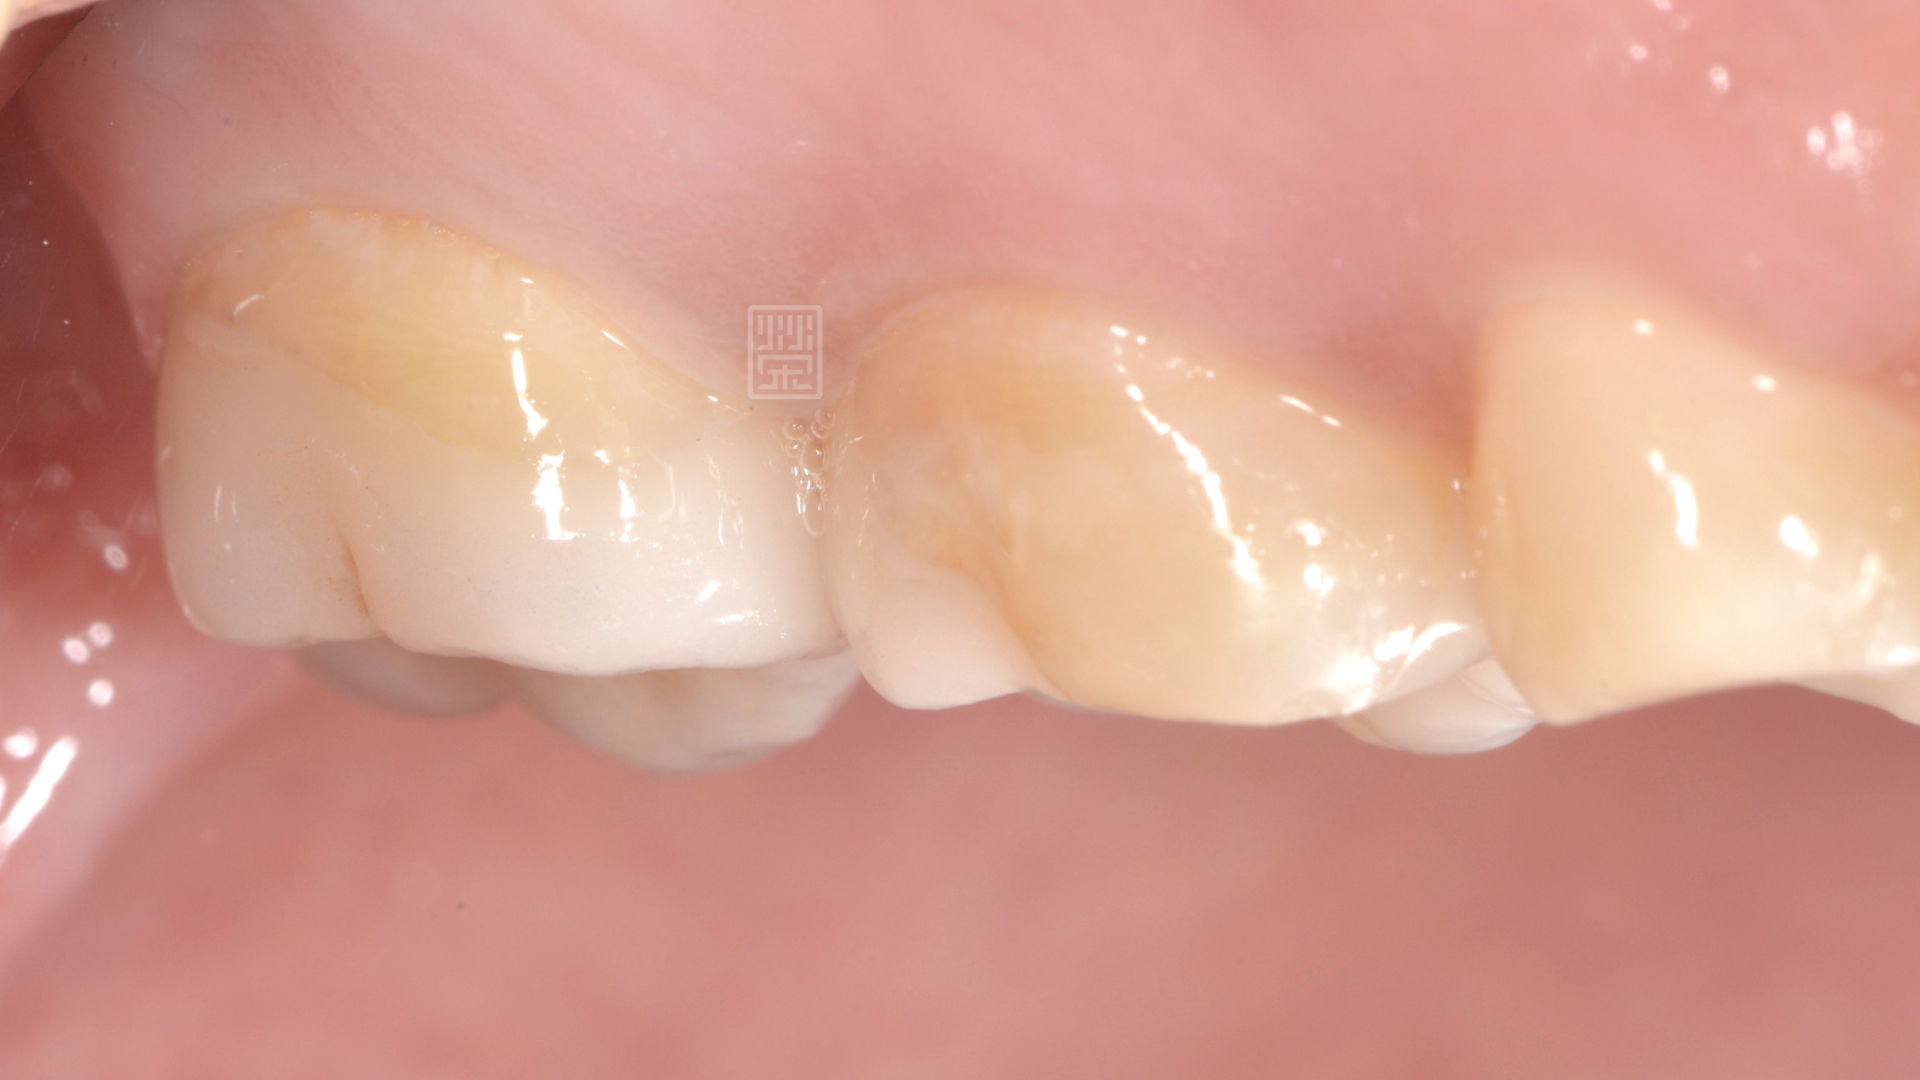

頰側大蛀牙

經由診斷後,應該是蛀牙造成牙齒損傷,咬到硬物,牙齒斷裂,幸運的是,牙齒神經依然健康,只是牙齒齒質受損嚴重,

陳小姐某天吃東西,突然發現好像咬到硬硬的,但仔細一看,似乎不是食物,而是自己的牙齒!!!而且牙齒就空了一個洞,緊張之餘,馬上安排門診檢查。